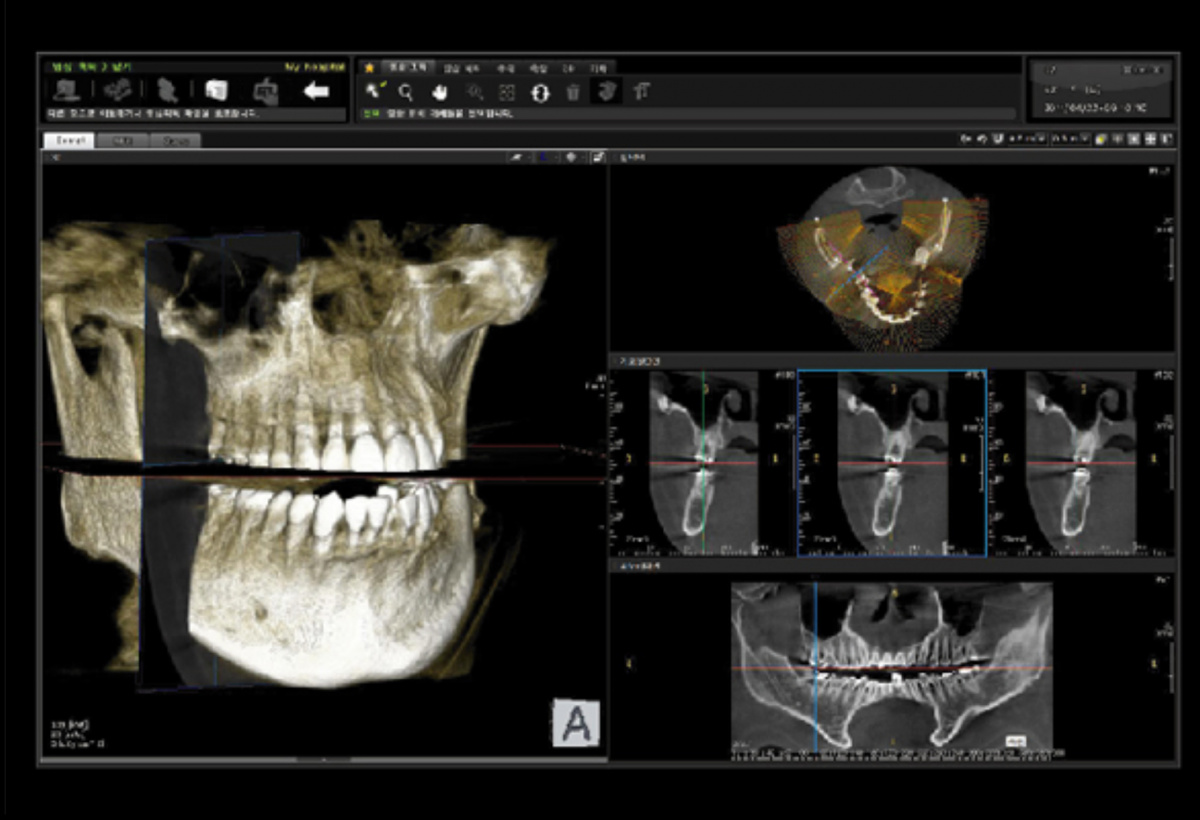

Немаловажным, а может главным вопросом, является универсальность программы-просмотровщика, в которой будут работать врачи-стоматологи. У Papaya 3D есть два варианта программ: Triana и OnDemand3D. Оба просмотровщика обладают схожим интерфейсом и имеют самые важные опции, а именно:

Таким образом обе программы являются простыми в пользовании, но обладающими обширным спектром возможностей для диагностики любыми специалистами-стоматологами. В данные программы происходит загрузка классических файлов DICOM 3.0, которые являются общепринятым форматом записи данных пациента. Это важный момент, так как позволяют врачу, имеющему полную версию программы загружать даже сторонние исследования и просматривать их в этих программах. Простота в освоении этих программ позволяет даже специалисту, не работающему раннее с этими программами, быстро адаптироваться и получить качественную информацию. Возможность выгрузки STL-файла дополнительно создает возможность интегрировать данные с цифровым ортопедическим протоколом.